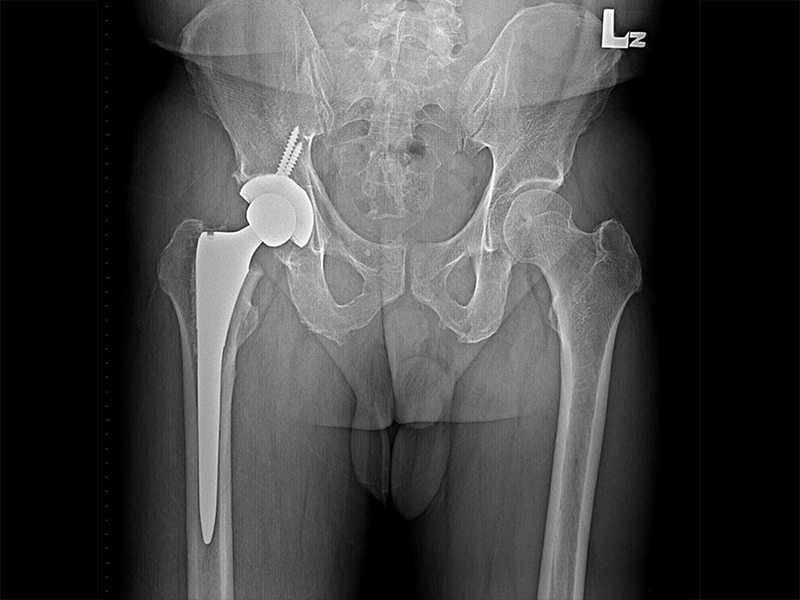

傳統髖關節置換